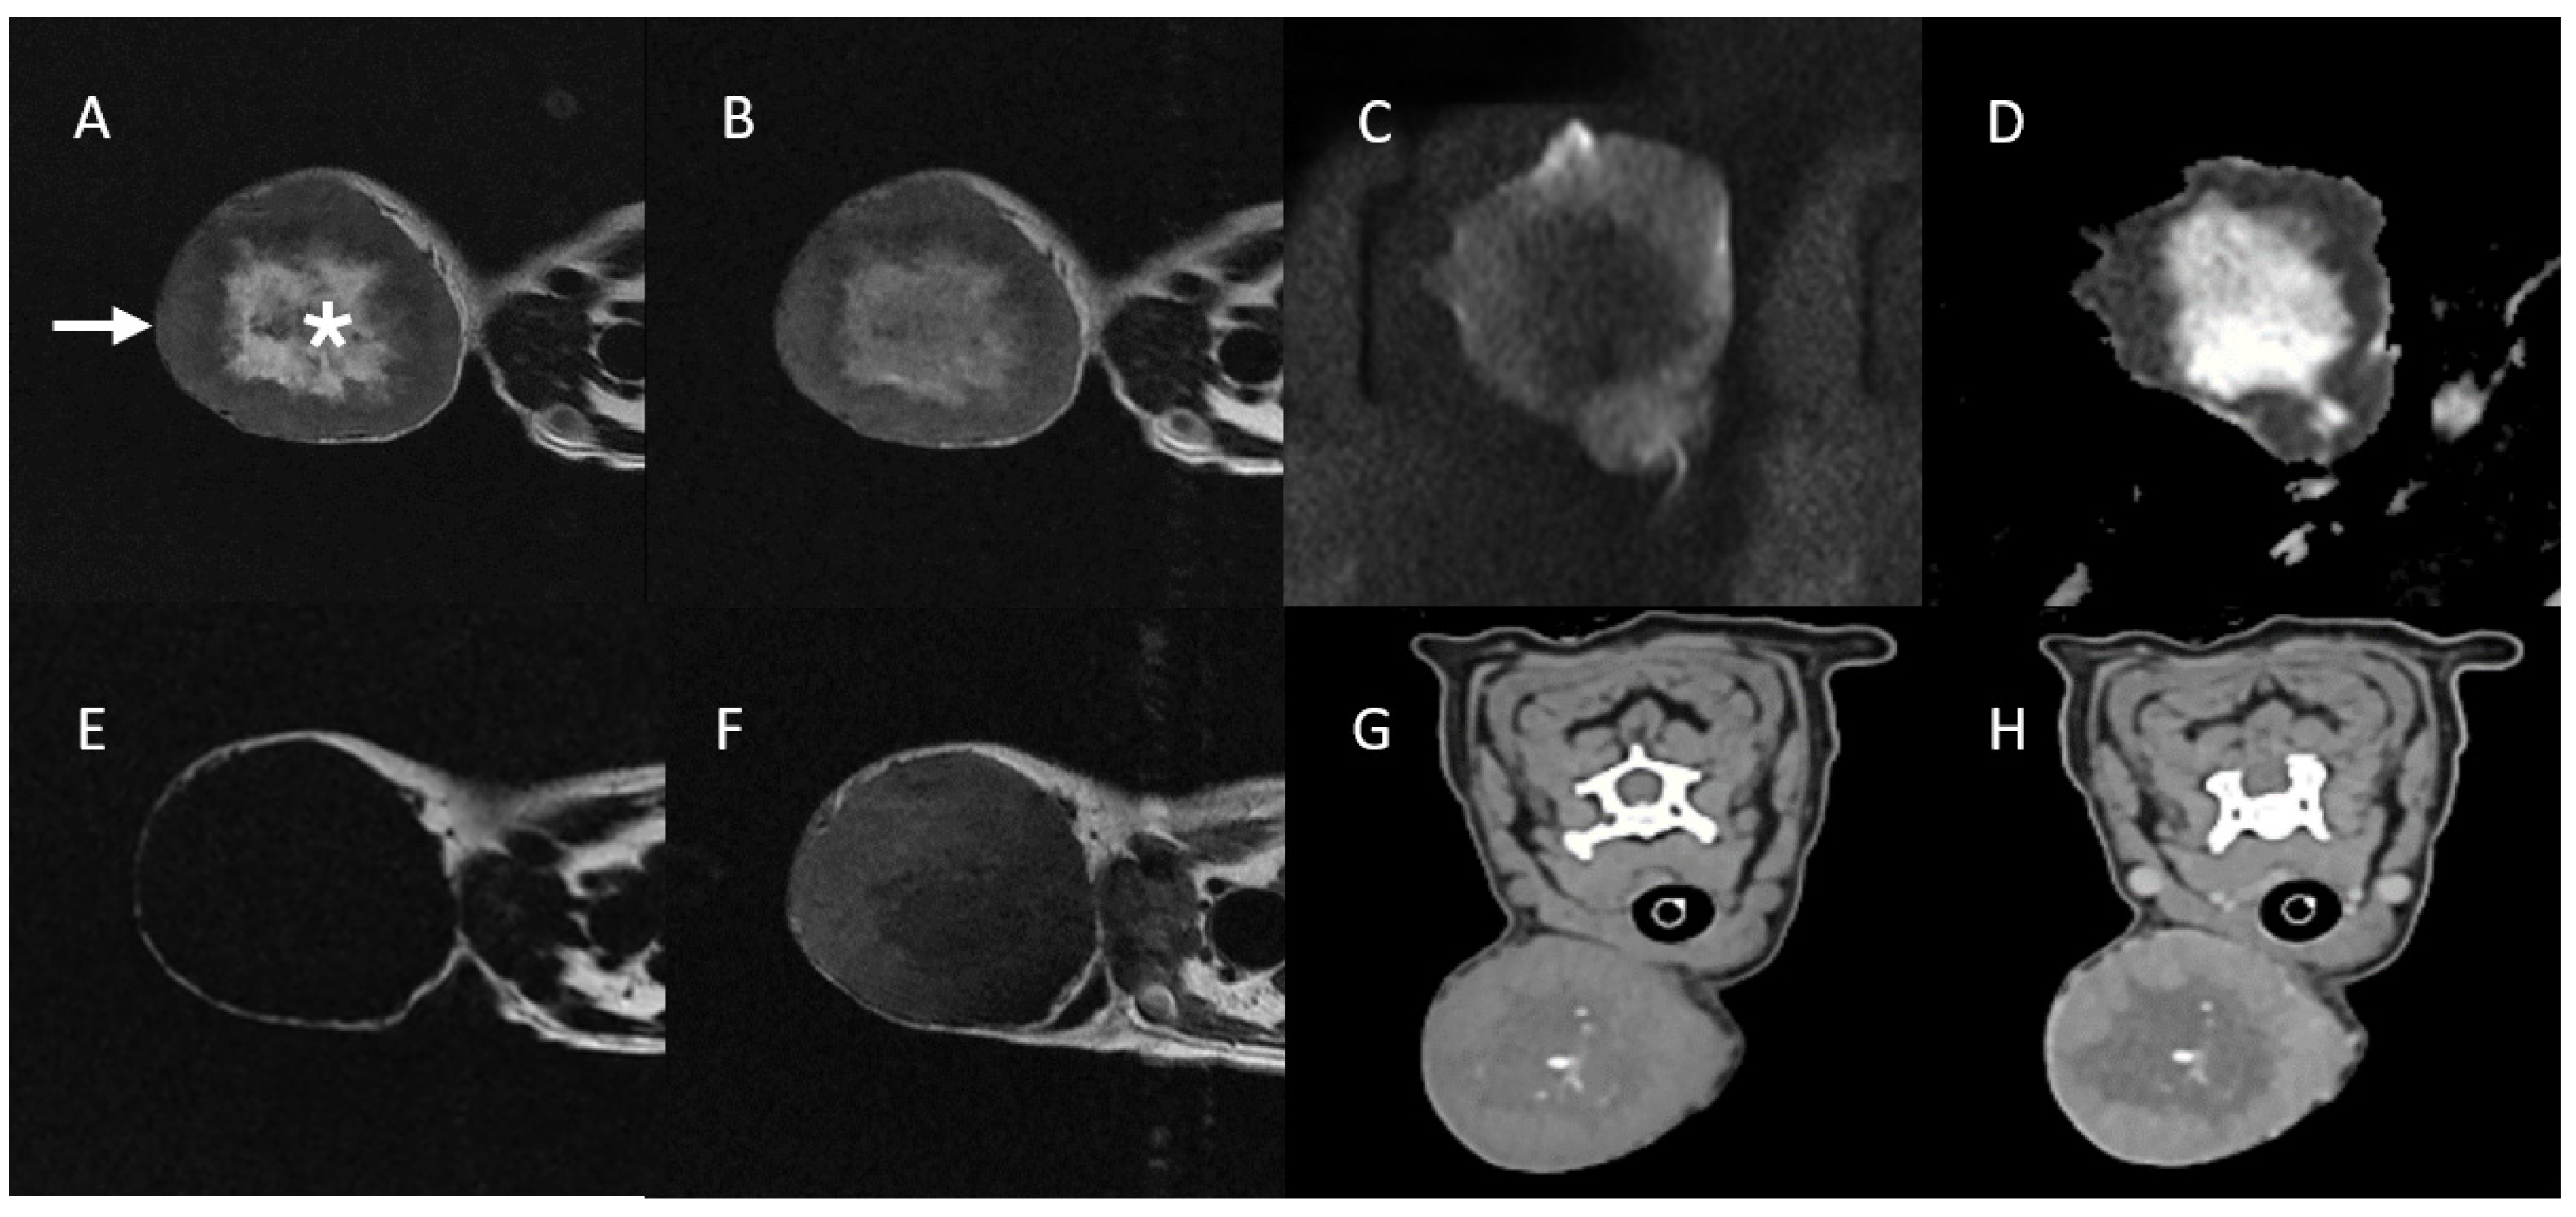

3.1. Case 1

| Mass Type | Soft Tissue Sarcoma (Hemangiopericytoma, Grade II) | Normal Region (Adjacent Muscle) | Soft Tissue Sarcoma (Myxosarcoma, Grade I) | Normal Region (Adjacent Muscle) |

| Ktrans (min−1), mean ± SD | 1.393 ± 0.026 (Peripheral mass region) 0.013 ± 0.079 (Central mass region) | 0.089 ± 0.042 | 0.176 ± 0.064 | 0.059 ± 0.141 |

| kep (min−1) mean ± SD | 5.137 ± 0.643 (Peripheral mass region) 0.992 ± 1.409 (Central mass region) | 0.381 ± 0.118 | 0.305 ± 0.108 | 0.699 ± 0.883 |

| Ve mean ± SD | 0.499 ± 0.107 (Peripheral mass region) 0.014 ± 0.043 (Central mass region) | 0.239 ± 0.089 | 0.585 ± 0.209 | 0.088 ± 0.115 |

| Vp mean ± SD | 0.241 ± 0.099 (Peripheral mass region) 0.011 ± 0.00006 (Central mass region) | 0.001 ± 0.00006 | 0.003 ± 0.00006 | 0.019 ± 0.045 |

| TIC Type | Fast wash-in, Fast wash-out (Peripheral mass region) Plateau (Central mass region) | Progressive | Progressive | Plateau |